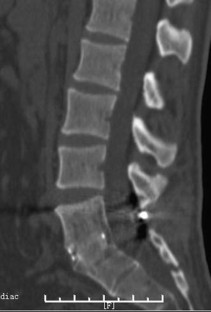

Fig. 1